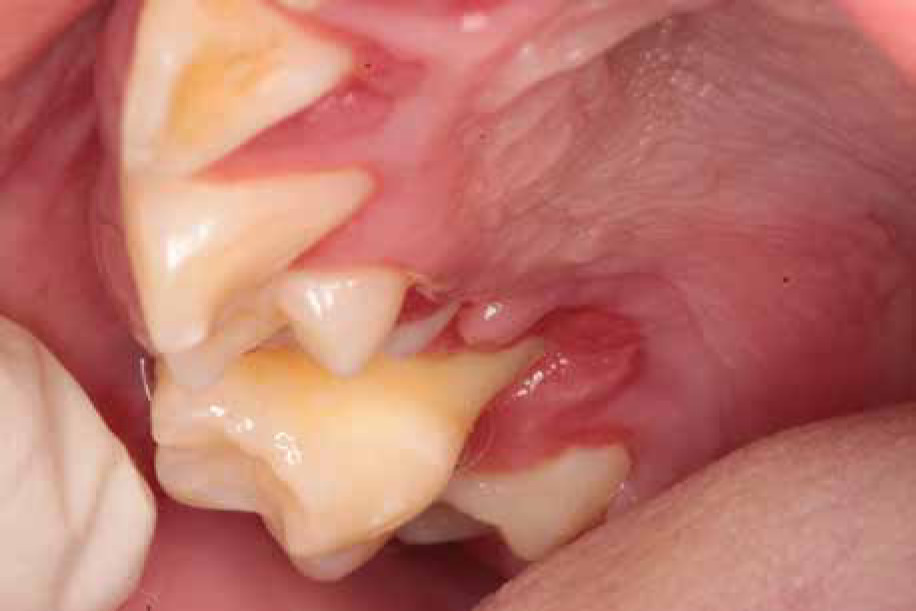

When he was 5 years of age the intraoral examination revealed incomplete primary dentition with five missing teeth, marginal gingivitis, interdental papilla hypertrophy, carious lesions in seven primary teeth, and one permanent tooth of various degrees of advancement for conservative treatment (Fig. 1). The patient was qualified for simultaneous dental treatment under general anesthesia. A panoramic radiograph picture was taken showing the advanced destruction of the alveolar bone in the maxilla and the alveolar part of the mandible. Three primary teeth were completely devoid of bone base. The roots of the lower incisors were only half of their normal length (Fig. 2). Under antibiotic protection (amoxicillin with clavulanic acid at a dose of 30 mg/kg), professional removal of dental plaque and conservative treatment of teeth extraction of four primary teeth with complicated caries and periodontitis were performed. The patient was provided with permanent dental care.